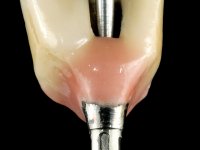

• Two months after implant placement and guided-bone regeneration, initiate the construction of a metal-ceramic fixed partial denture with two elements screwed on the dental implant.

With the implant osteo-integrated with did an impression (open-tray technique) and the dental technician started the construction of a gold framework. The use of an abutment made of a gold alloy allowed us to do a framework with a perfect fit.

During the framework try-in, the color survey was done in order to proceed with the ceramics placement, with a crown and gingiva-components.